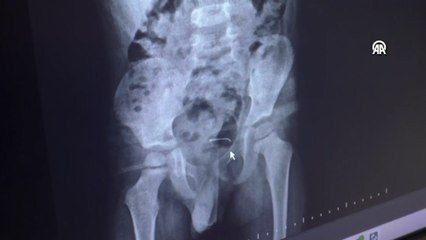

Çin'de tıp dünyasını şaşırtan bir olay yaşandı. Çinli uzmanlar, Yunnan eyaletinde yaşayan 5 yaşındaki Xiao Tao adlı çocuk nefes darlığı ve boğaz kaşıntısı şikayetiyle hastaneye başvurdu. Yapılan kontrollerde,Tao adlı çocuğun boğazında yaşayan solucan tespit edildi. Uzmanlar, Tao'yu ameliyata aldı. Yaklaşık 4 saat süren operasyonda, canlı solucanın bir yıldan fazla çocuğun midesinde yaşadığı ve solunum problemleri ile sürekli boğaz ağrısına neden olduğunu belirtti. Yapılan operasyonla Tao'nun boğazındaki solucan çıkarılırken, çocuğun sağlık durumunun iyi olduğu ifade edildi.